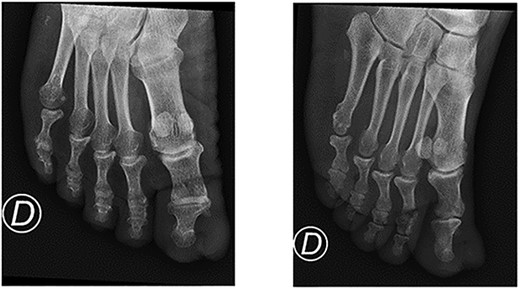

A 64-year-old sub-Saharan African male with diabetes with a long-standing history of a recurring slow-growing periungual mass of the left great toe after multiple surgical wedge excisions for an ingrown toenail presented to the emergency department with acute pain, bleeding and local swelling of the lesion. Physical examination revealed a painful periungual mass (Fig. 1). The toe’s range of motion was conserved and there was no sign of ischemia. An X-ray was performed and did not reveal any bone erosion or osteolytic lesions (Fig. 2). Neither computer tomography (CT) scanning nor magnetic resonance imaging (MRI) were performed. The emergency doctor initially treated the lesion with silver nitrate treatment, and the patient was referred for an orthopaedic consultation for treatment of a recurrent ingrown toenail.